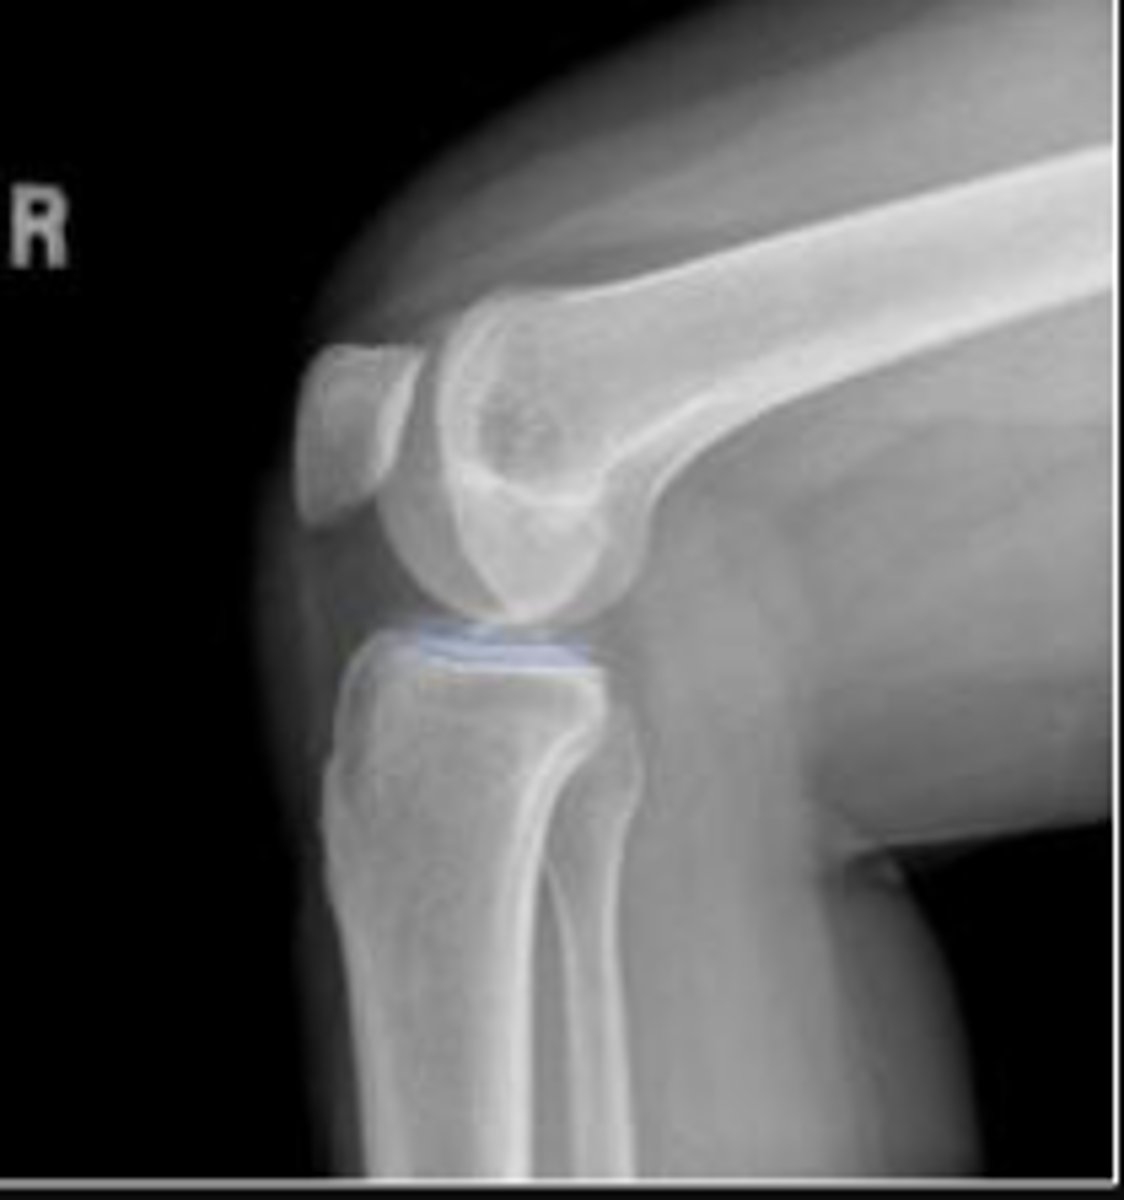

Lipohemarthrosis

What are the arrows pointing to?